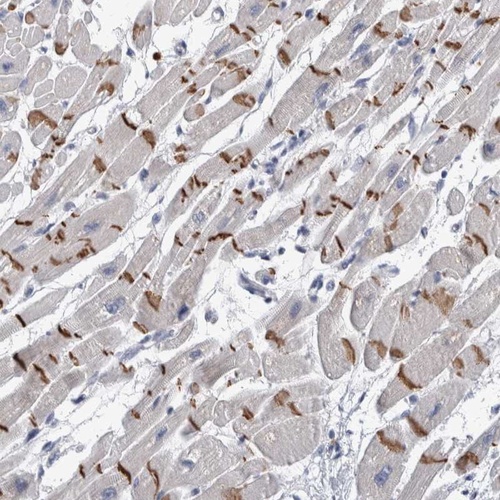

Immunohistochemical staining of human heart muscle shows distinct positivity of intercalated discs in myocytes.